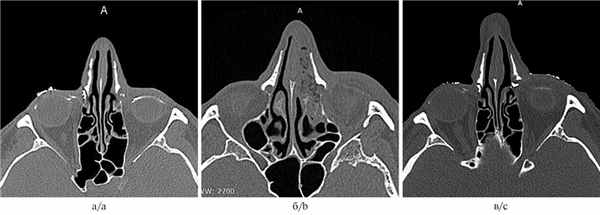

В 2019 г. в НИИ глазных болезней обратился пациент К., 50 лет, с диагнозом: левосторонний хронический дакриоцистит, облитерирующая форма. Диагноз был установлен с учетом данных компьютерной томографии, выполненной с контрастированием слезоотводящих путей (рис. 1, а). При изучении сканограмм обращало на себя внимание истончение слезной кости и лобного отростка верхней челюсти.

Рис. 1. Результаты компьютерной томографии (костная реконструкция).

а — до операции; б — в 1-е сутки после операции; в — через 6 мес после операции.